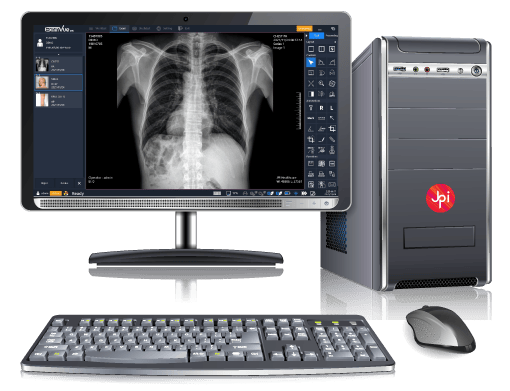

Acceso Seguro y Rápido a tus Imágenes Médicas

En LinkMedic llevamos la radiología al siguiente nivel con nuestro sistema PACS en la nube. Procesa, comparte y almacena radiografías digitales de forma eficiente y sin límites geográficos. Garantizamos acceso seguro, imágenes de alta calidad y una experiencia ágil que optimiza tu flujo de trabajo, mejorando la atención de tus pacientes en cualquier momento y lugar.

PACS DE EXAMVUE

EXAMVUE DUO ACQUISITION SOFTWARE

Diseñado para optimizar la captura de imágenes radiográficas con la más alta calidad y eficiencia